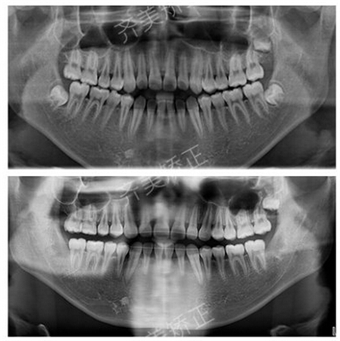

牙齿问题:牙齿错合

治疗周期:1年半多

这就是开合!